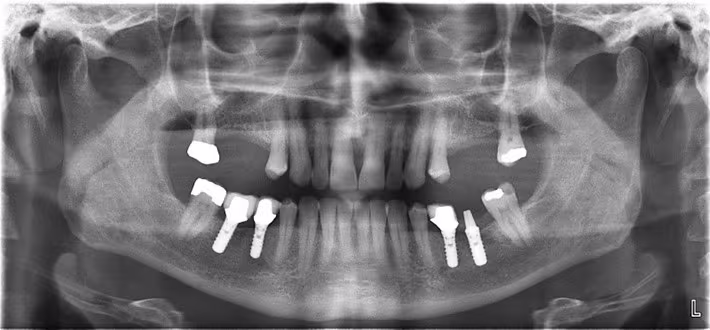

Figure 22. Panoramic Image with Minor Errors.

This panoramic image demonstrates a slight downward tilt of the patient’s head evidenced by a minor grin of the occlusal plane, slight foreshortening of the mandibular incisor teeth. In addition, the tongue was not placed against the palate. However, these minor errors do not interfere with the overall diagnostic acceptability of the image.